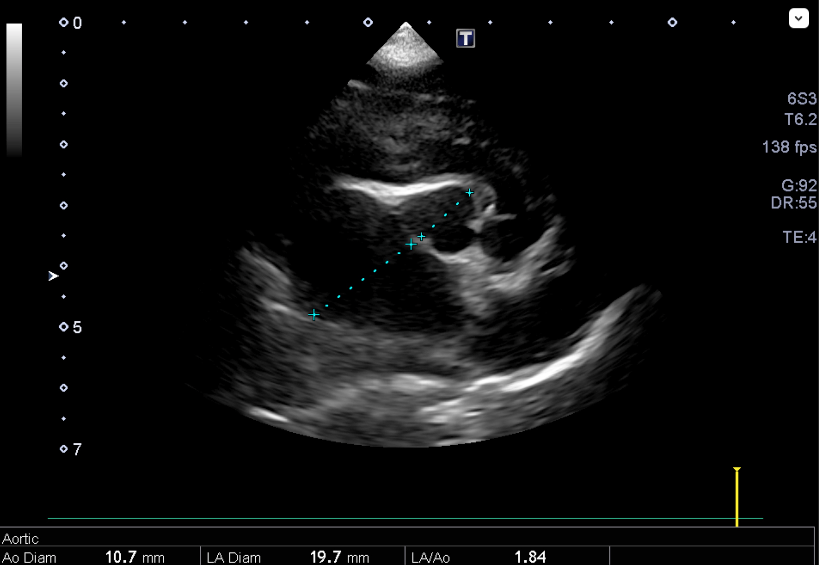

心臓エコー内服開始0日目